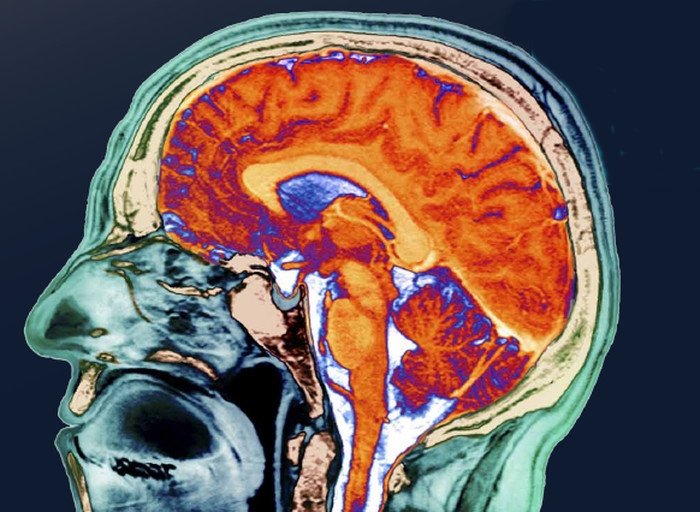

Мозг человека — принципы его работы, возможности, пределы физиологической и психической нагрузки — продолжают оставаться для исследователей одной большой загадкой. Несмотря на все успехи в его изучении, объяснить, как мы мыслим, понять механизмы сознания и самосознания ученые пока не в состоянии. Накопленных знаний о работе мозга, впрочем, достаточно, чтобы опровергнуть некоторые распространенные мифы о нем. Что ученые и сделали.

Средний объем мозга современного человека — около 1400 кубических сантиметров, это довольно большая величина для наших размеров тела. Большой мозг человек отрастил себе в ходе эволюции — антропогенеза. Наши обезьяноподобные предки, не имевшие больших когтей и зубов, спустившись с деревьев и перейдя к жизни на открытых пространствах, стали развивать мозг. Хотя это развитие не сразу пошло быстро — у австралопитеков объем мозга (около 500 кубических сантиметров) практически не менялся шесть миллионов лет. Скачок в его увеличении произошел два с половиной миллиона лет назад. У ранних Homo sapiens мозг уже значительно вырос — у Homo erectus (Человека прямоходящего) его объем составляет от 900 до 1200 кубических сантиметров (это перекрывается диапазоном мозга современного человека). У неандертальцев мозг был уже очень большим —1400-1740 кубических сантиметров. что в среднем больше, чем у нас. Ранние Homo sapiens на территории Европы — кроманьонцы — просто заткнут нас за пояс своим мозгом: 1600-1800 кубических сантиметров (правда, кроманьонцы были высокими — 180-190 сантиметров, а антропологи находят прямую связь между размером мозга и ростом).

Мозг в эволюции человека не только увеличивался, но и менялся по соотношению разных частей. Палеоантропологи исследуют мозг ископаемых гоминид по отливке из черепа — эндокрану, который показывает относительный размер долей. Быстрее всего развивалась лобная доля, что связано с мышлением, сознанием, появлением речи (зона Брока). Развитие теменной доли сопровождалось совершенствованием чувствительности, синтеза информации от разных органов чувств и тонкой моторики пальцев рук. Височная доля поддерживала развитие слуха, обеспечивающего звуковую речь (зона Вернике). Так, например, у эректусов мозг вырос в ширину, увеличилась затылочная доля и мозжечок, но лобная доля оставалась низкой и узкой.

И у неандертальцев в их очень большом мозге лобная и теменная доля были развиты относительно слабо (по сравнению с затылочной). У кроманьонцев мозг стал значительно выше (за счет увеличения лобных и теменных долей) и приобрел сферическую форму.

Итак, мозг наших предков рос и рос, но, что парадоксально, около 20 тысяч лет назад началась обратная тенденция: мозг стал постепенно уменьшаться. Так что у современных людей средний размер мозга меньше, чем у неандертальцев и кроманьонцев. В чем причина?

А магнитно-резонансная томография (МРТ) регистрирует активность тех или иных областей во время разных видов деятельности. Но карта мозга не абсолютна, и появляется все больше доказательств, что все устроено намного сложнее. Например, в процесс речи вовлечены не только известные зона Брока и зона Вернике, но и другие части мозга. А мозжечок, который все время связывали с координацией движений, участвует в самых разных видах мозговой деятельности. С вопросом, есть ли в мозге специализация, мы обратились к Ольге Сварник: «В мозге есть специализация на уровне нейронов, и она достаточно постоянна, — ответила специалист. — Но выделить специализацию на уровне структур сложнее, потому что совершенно разные нейроны могут лежать рядом. Можно говорить о скоплении нейронов, типа колонок, можно говорить о сегментах нейронов, активирующихся в один и тот же момент, но невозможно реально выделить какие-то крупные области, которые принято выделять. МРТ отражает активность кровотока, но не работу отдельных нейронов. Наверное, по картинкам, которые получают по МРТ, мы можем сказать, где с большей или меньшей вероятностью можно найти те или иные специализации нейронов. Но говорить о том, что какая-то зона за что-то отвечает, мне кажется неправильным».